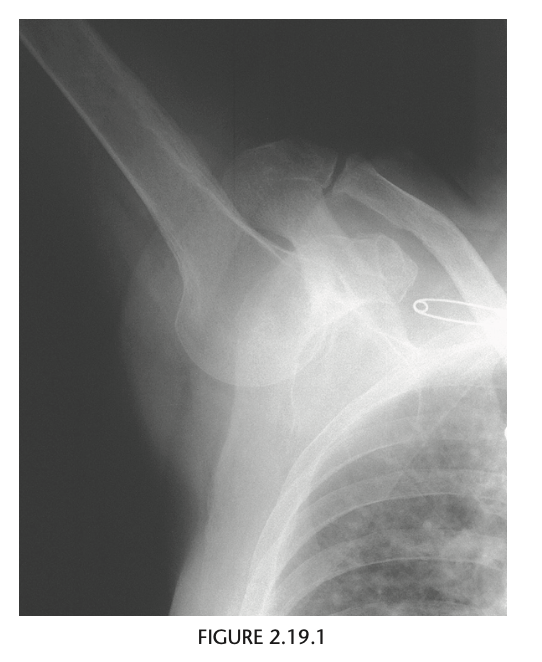

18

An anteroposterior radiograph was obtained for an 81-year-old man who fell. He entered the

emergency room with his arm locked in an abducted position high above his head.

The right humeral head is dislocated infe-

riorly at the glenohumeral joint. The superior aspect

of the humeral head does not contact the inferior

aspect of the glenoid rim, and the arm is held over

the patient’s head in a fixed position.

Luxatio erecta

With luxatio erecta, the inferior joint capsule is

almost always torn. There may also be associated fractures of the greater tuberosity, acromion, clav-

icle, coracoid process, and glenoid. The most seri-

ous complications are injuries to the brachial plexus

and axillary artery.